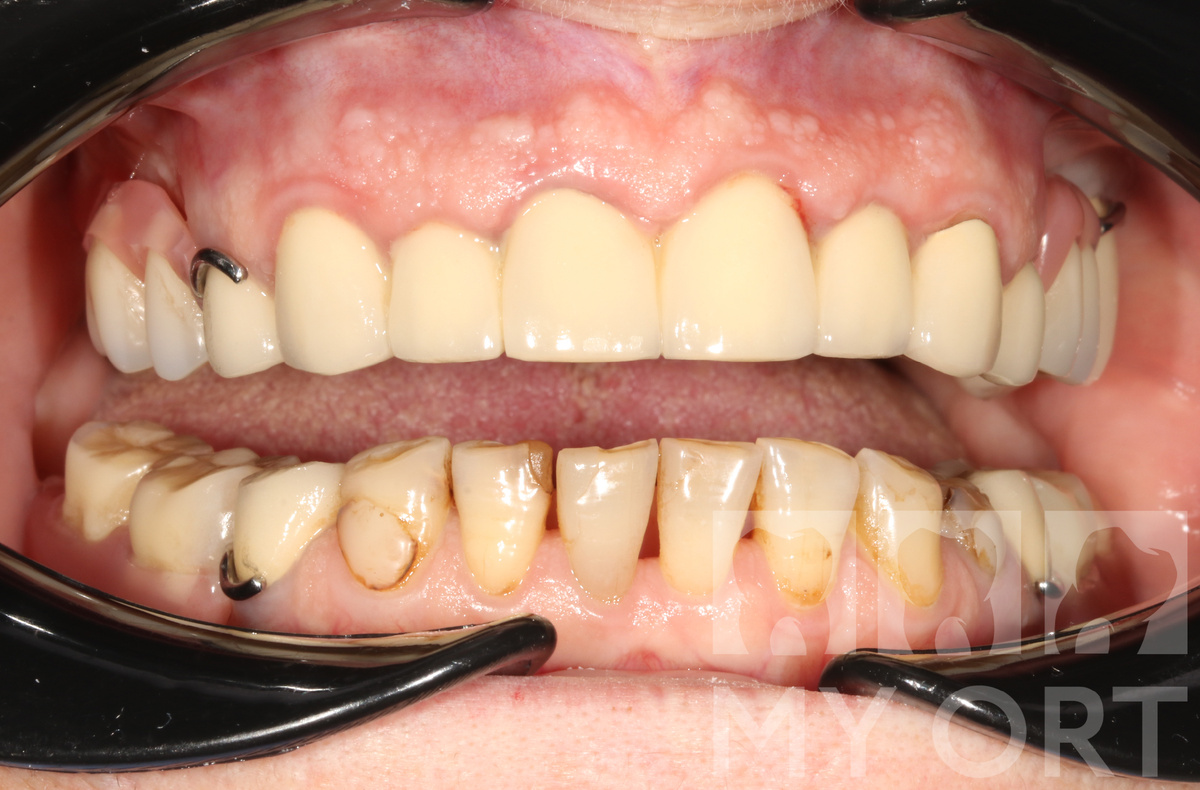

• Десна нормализовалась и стала бледно-розового цвета, без признаков воспаления и кровоточивости

• Новые мостовидные протезы плотно прилегают к десне, исключая оголение шеек.

• Пациентка довольна внешним видом новых конструкций

• А главное - было обеспечено плотное прилегание конструкций к десне для предотвращения воспаления

Конечный результат